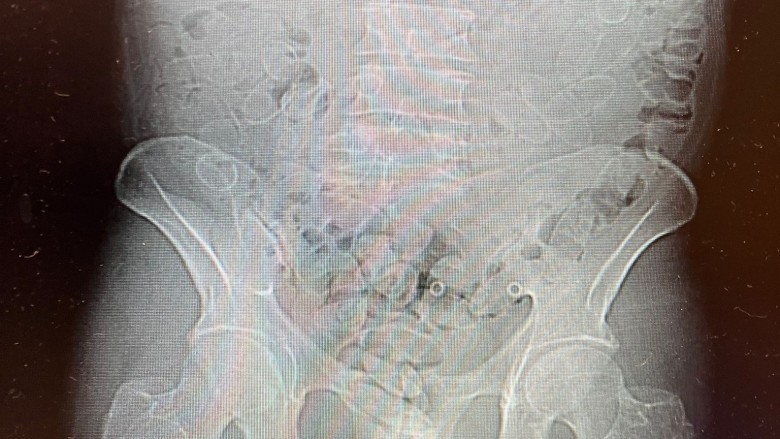

Na tym jednak sprawa się nie skończyła. Funkcjonariusze zwrócili uwagę na nerwowe zachowanie podróżnego, które mogło wskazywać, że przewozi narkotyki również wewnątrz organizmu. 40-latek przyznał później, że połknął 88 kolejnych kapsułek z kokainą. Został przewieziony do szpitala, gdzie wykonano badanie tomografem komputerowym. Wynik potwierdził obecność narkotyków w jego ciele.